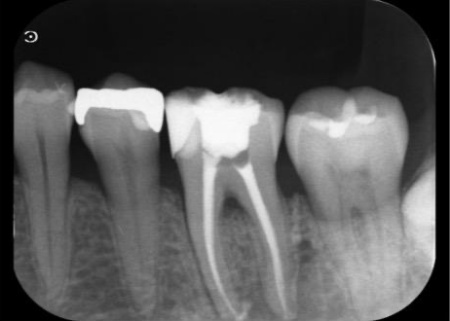

レントゲンを撮影して詳しく調べたところ、歯の奥側の根の先端部分に骨が溶けたことで黒く透けて見える透過像が確認されました。

この透過像は歯の神経や血管が通る管「根管」の内部で細菌感染が起こり、根の先にまで炎症が広がっているサインです。

マイクロスコープを用いて根管の内部を確認したところ、この歯には4本の根管がありました。

最後に、治療後のレントゲンで4本すべての根管に充填材が緊密に行き渡っていること、処置部位に問題がないことを確認して、治療を終了しました。